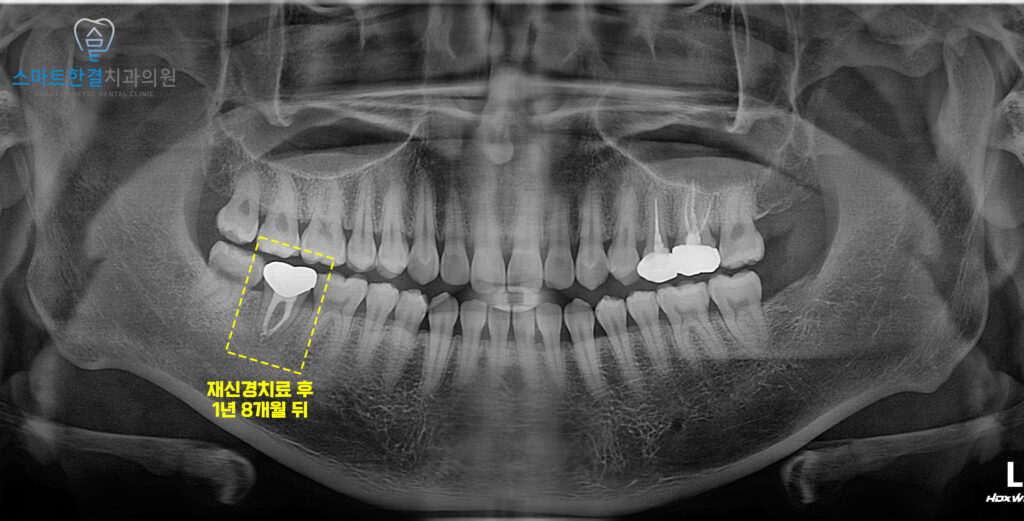

위 사진은 신경치료 후

1년 8개월이 지난 사진으로

뿌리 끝 잡혀있던 병소도 전부 사라지고

증상도 없어졌어요.

화서동치과 스마트한결치과의

재신경치료 전후 사진이에요.

환자분께서는 신경치료를 받았던 치아의 염증이 생겨

살리지 못하고 발치를 해야할까 싶어

걱정을 많이 하셨으나

재신경치료를 통해 살리게 되어 다행이라며

만족해 주셨어요.